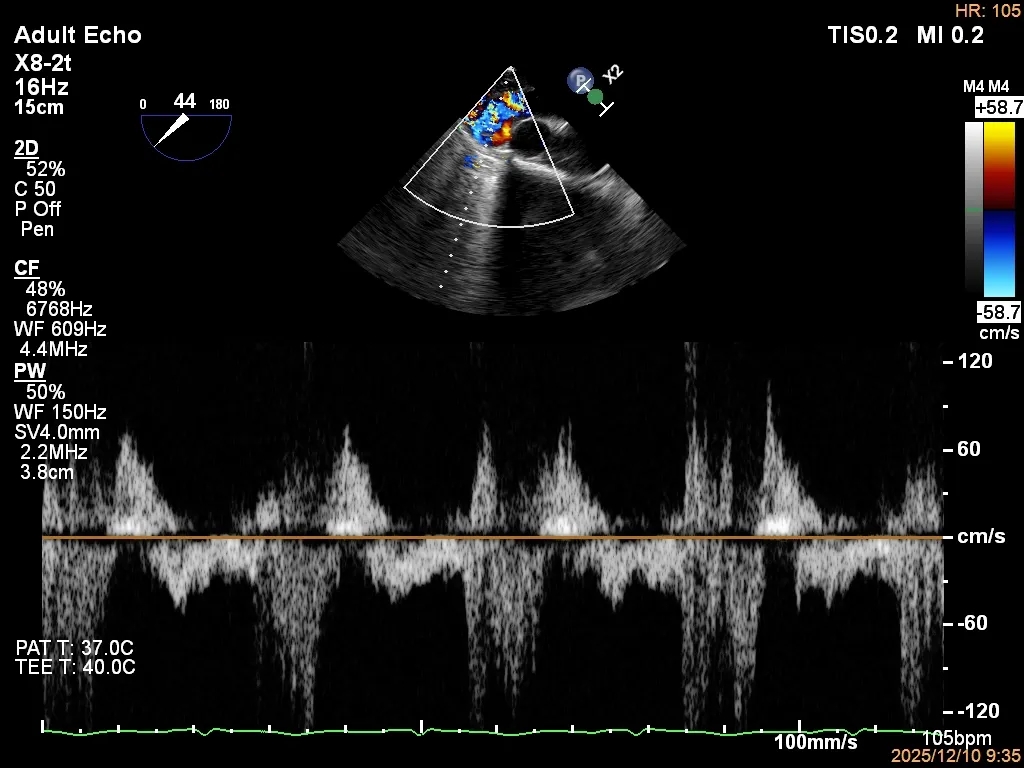

四条肺静脉均可测及收缩期反向血流

肺静脉收缩期逆流消失,频谱形态基本恢复正常

术后2D TTE:

术后TTE可见二尖瓣微量-轻度反流,三尖瓣反流明显改善降至中度